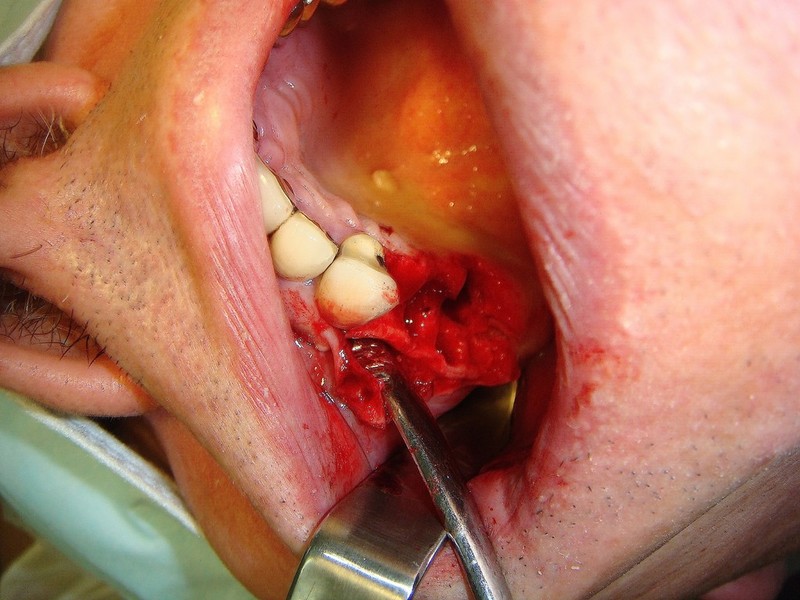

Implantologia avanzata con contestuale rimozione impianti e cisti

Video di una Parte dell'intervento in cui si puo' vedere la comunicazione tra impianti rimossi e pavimento nasale.

Estrazione di un canino incluso e contestuale inserimenti di impianto e innesto osso eterologo